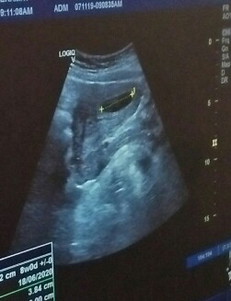

kantung

normal ke kalau kantung mcm ni ?

Ikut size kantung dlm screen 8 w+